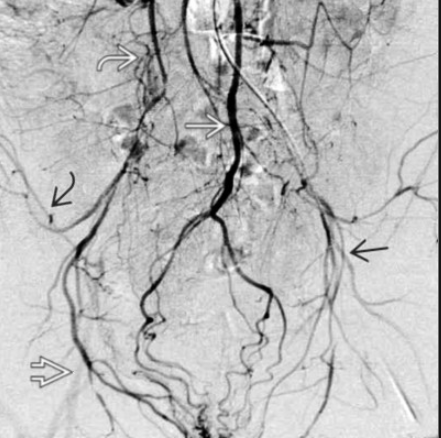

Leriche syndrome = abdominal aortic or iliac artery occlusive disease that causes absent femoral pulses, bilateral buttock claudication, and impotence. Surgical therapy (aorto-bi-iliac or aorto-bifemoral bypass) is the treatment of choice.

pic here showing IMA continues as the superior hemorrhoidal artery and communicates with multiple gluteal collaterals that reconstitute a faintly opacified right common femoral artery . There are also iliolumbar and deep circumflex femoral artery collaterals present